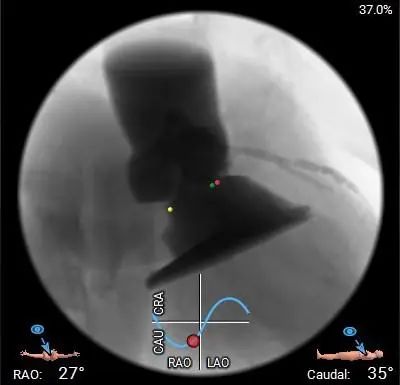

术中影像

最终工作位置